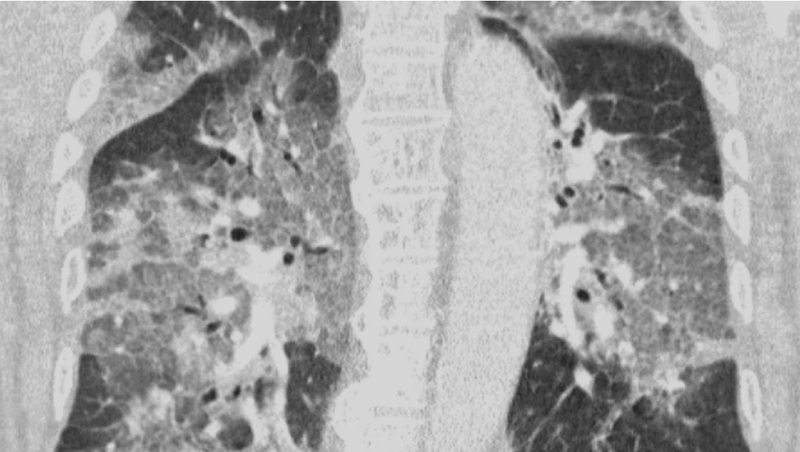

Ya se empiezan a notar las primeras consecuencias del miedo a los efectos secundarios de la vacuna de AstraZeneca contra la COVID-19, que está provocando el rechazo de algunas personas a recibir una dosis de la vacuna. Médicos holandeses han compartido las imágenes de las radiografías de los pulmones de un paciente, ingresado ahora en la UCI, que se negó a inyectarse la dosis por miedo. Los doctores intentan concienciar a las personas sobre lo que provoca el coronavirus y animar a la vacunación.

Los médicos también han publicado una carta abierta dirigida al ministro de Sanidad del país, Hugo de Jonge, sobre la paralización del uso de vacunas contra el coronavirus. En la carta relatan el ingreso en la UCI de un paciente no vacunado y cómo lucha contra le enfermedad con respiración asistida. "Oímos el tremendo pesar en su voz y la desesperación en sus ojos. El virus lo ha atacado y podría haberse evitado. Con su permiso, compartimos su escáner de pulmón. No es necesario ser un especialista en pulmones para reconocer la devastación, ni epidemiólogo para explicar los riesgos de no estar vacunado", cuentan.